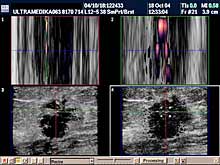

- ako postoji promena i mikrokalcifikacija obavezna je primena: 3D Sono CT i 3D CPA i Broad

band-CD i CPD,

- ako postoji sumnja na zloćudnu promenu pored navedenog

potrebna je procena morfologije i krvnih sudova regionalnih limfnih

žlezda.

Primenjena tehnika:

- 2D broad band,

- Sono

CT,

- XRes,

- 3D Sono CT,

- Broad band - CD i CPD,

- 3D CPA.